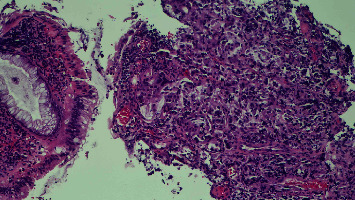

肛周帕吉特氏病(PPD)是一种罕见的皮肤腺癌,发生于肛周的分泌腺。它常被误诊为湿疹、白斑病、鳞状细胞癌、鲍温氏病、扁平苔藓或尖锐湿疣。我们报告了一例 63 岁男性患者的病例,他因肛门肿块持续 6 个月之久到急诊室就诊。经检查发现,患者患有直肠腺癌,并伴有腺样体扩散,患者接受了新辅助化疗,症状有所改善。然而,患者拒绝接受进一步化疗和腹部会阴部切除与重建计划,因为这需要永久性结肠造口。

Perianal Paget's disease (PPD) is a rare skin adenocarcinoma that arises in the apocrine glands of the perianal region. It is often misdiagnosed as eczema, leukoplakia, squamous cell carcinoma, Bowen's disease, lichen planus, or condylomata acuminata. We report a case of a 63-year-old male who presented to the emergency room (ER) for evaluation of an anal mass that had persisted over 6 months. The patient was found to have a rectal adenocarcinoma with pagetoid spread and underwent neoadjuvant chemoradiation with symptom improvement. However, the patient declined further chemotherapy and the planned abdominal perineal resection with reconstruction, as it would require a permanent colostomy.